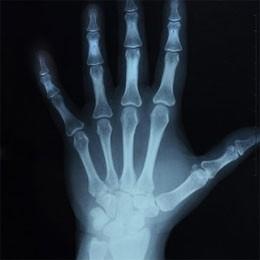

Osteoporosi: perché con il passar degli anni le ossa possono perdere calcio e diventare più fragili? Come è possibile prevenire e rallentare questa patologia che colpisce prevalentemente le donne? Lo chiederemo al professor Ranuccio Nuti, direttore del dipartimento di medicina interna e malattie metaboliche dell’Università di Siena.